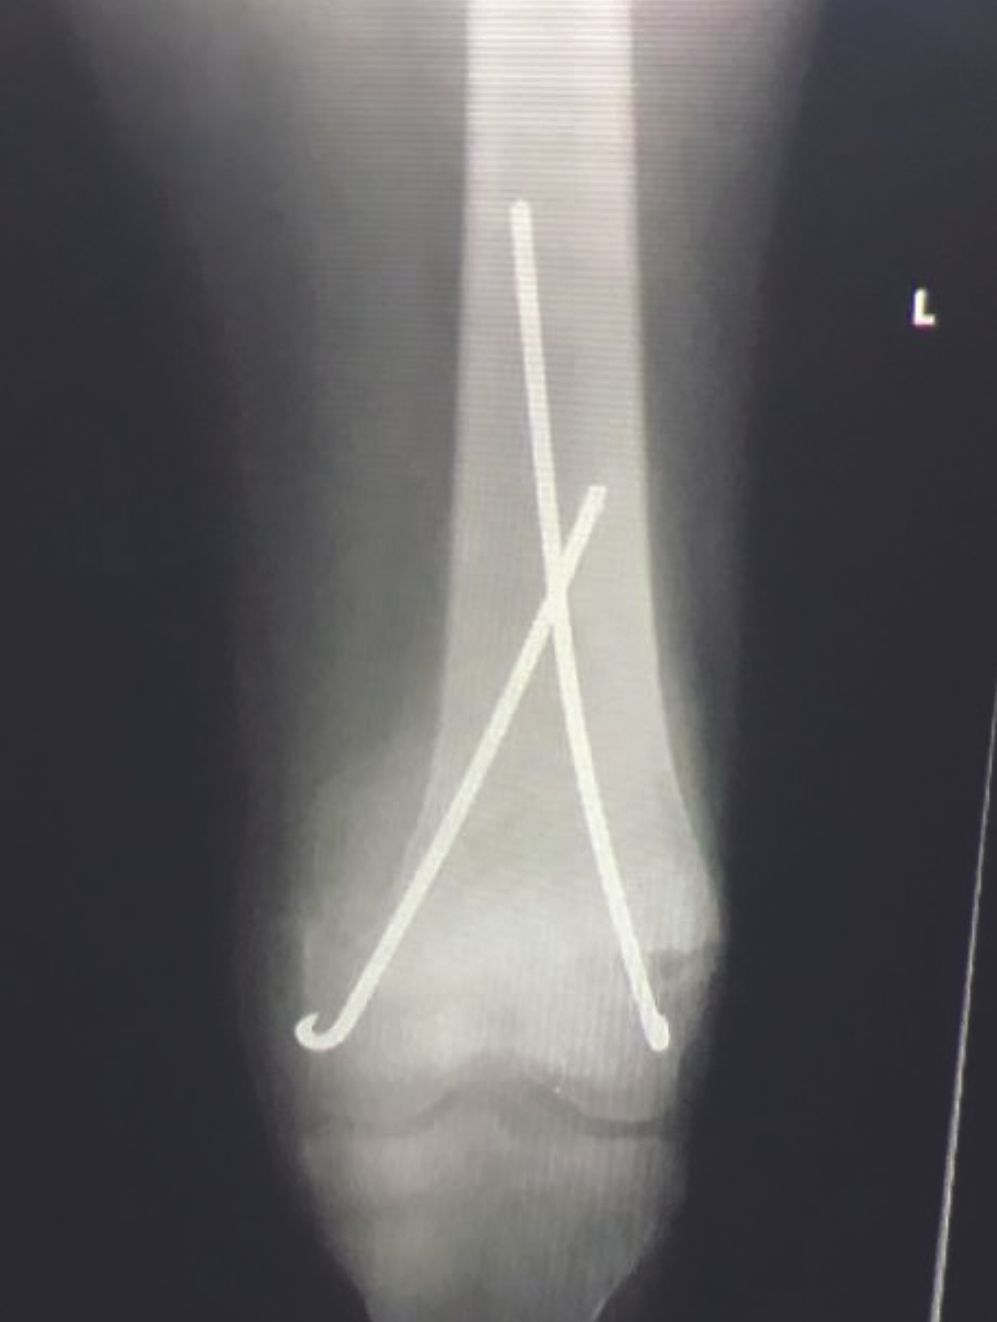

Whilst the spectrum of orthopaedic pathology is as wide as in first world countries the pathology is usually much more advanced with a preponderance of paediatric pathology, infection and neglected trauma. Local deficiencies with theatre sterility, lighting, electricity, X-ray and surgical supplies will dictate that techniques need to be tailored to the local circumstances. Percutaneous techniques with wires for many upper limb fractures are as good as locked plates but significantly cheaper and safer. (Fig 5)